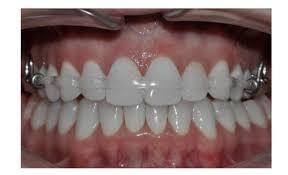

①透明維持器(clear overlay):目前主流,最常被用,因為美觀輕巧。

其實隱形牙套(例如隱適美、時代天使、舒服美、icot等等百花齊放的品牌)就是由此分支而出(材料不同而已,工序類似,美白牙套最軟、隱形牙套有點硬但有彈性、維持器較硬),正常的社交距離真的不太容分辨的出,真的是不知不覺在變美麗(旁人的觀點啦,牙齒在移動時的痛還是有的,只有自己知,如人飲水)。以口腔保持清潔的觀點,對牙周、蛀牙等牙科大宗問題,最有幫助,因為可取下好好刷牙。

透明維持器(clear oerlay)口內照,跟隱形牙套很像吧

透明維持器(clear overlay),跟隱形牙套很像吧

④QCM其實就跟其實就跟透明矯正器一樣,都只是前牙美觀區的障眼法,在較不被看見的後牙區,一樣有金屬的部分,而且,透明矯正器(不管是陶瓷、水晶...等等),為了美觀,都有一定程度的犧牲,例如矯正器尺度,為了達到一定強度(矯正是個漫長的療程),往往得做厚一點(臨床意義就是,凸凸的異物感更明顯、更容易刮黏膜)。我特地找這兩張圖說明,給愛美人士看一下,減少誤會,即使矯正器是透明不明顯的,矯正線...那條鐵絲(雖有白色的矯正線.....),別人仍是看的見,仍然是國王的新衣,才會後來演進出隱適美等隱形牙套矯正的市場....所以其本質是一樣的喔,換湯不換藥,我文章開頭有說了。那跟功能性矯正,是完全不一樣的思路。

透明/陶瓷/水晶矯正器